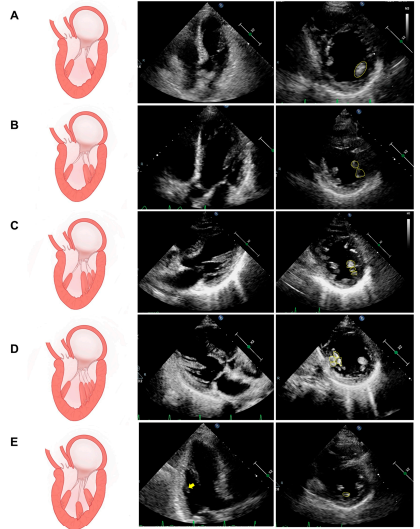

Figura 1. Esquemas e ecocardiogramas de variantes comuns em termos do número de colunas de músculos papilares (MP). (A) Um MP típico com um único músculo. (B) Duas colunas de musculares paralelas de MP. (C) Três colunas de musculares paralelas de MP. (D) Quatro colunas de musculares paralelas de MP. (E) O MP acessório (ou seja, MP intermediário, a seta amarela)